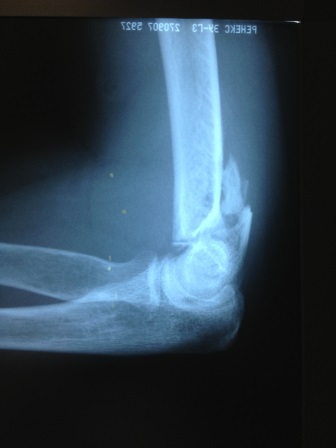

Особую сложность представляют внутрисуставные и внесуставные переломы плечевой кости в области локтевого сустава в виду сложной биомеханики сустава и близости расположения сосудисто-нервных пучков. Подобные травмы происходят в результате падения на согнутую в локтевом суставе руку. Высок риск развития посттравматического артроза в долгосрочной перспективе.

Рис. 3. Пациентка, 52 года. Закрытый внутрисуставной оскольчатый перелом нижней трети правой плечевой кости со смещением костных отломков. Закрытый внутрисуставной перелом локтевого отростка правой локтевой кости со смещением костных отломков.

Только точная репозиция отломков позволяет восстановить суставные поверхности. Восстановление суставных поверхностей является самой главной задачей при лечении подобных переломов. То, как сустав и вся рука будут функционировать в дальнейшем, зависит от успешного выполнения данной задачи. Эти травмы чрезвычайно сложны для лечения.